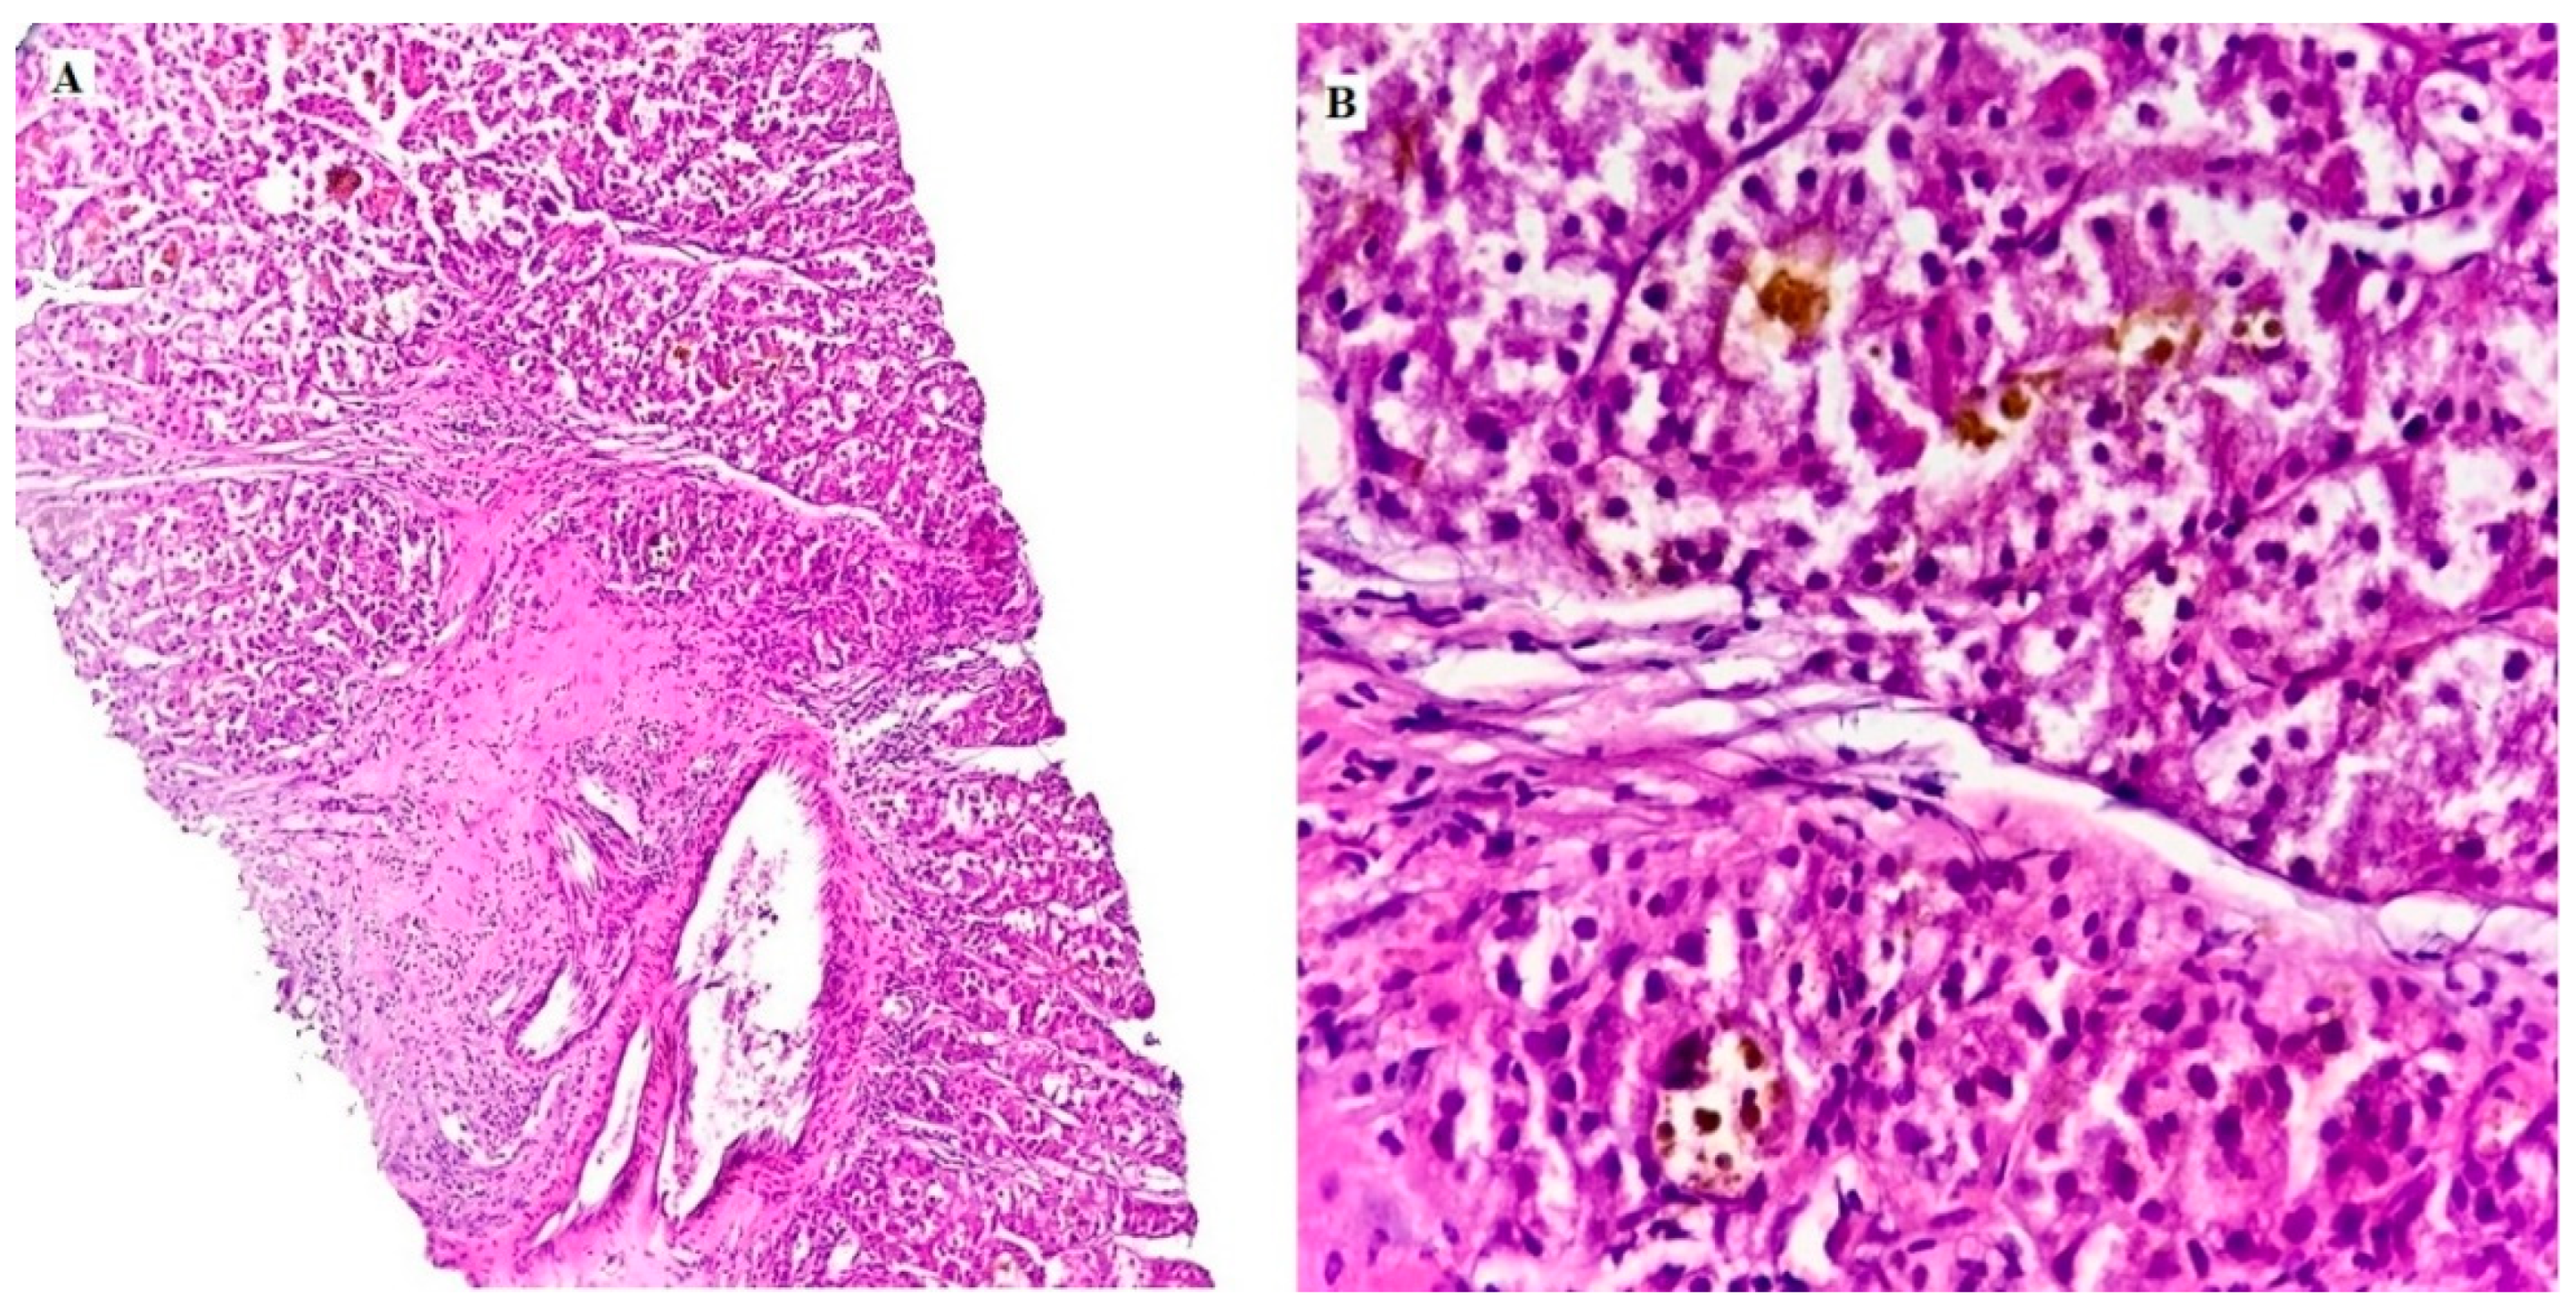

3. Results

3.1. EpCAM Expression in Different Studied Cases